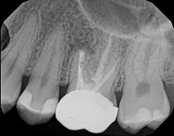

Missed canals and sclerotic orifices/canals:

Before

4-month post-opIn this situation, some would say the canals are so “calcified” that root canal treatment can’t be done; or sometimes the canal can’t be found. And because of that the tooth would need an extraction and an implant. In some instances, root canal therapy can’t be done but that does not mean the tooth is a loss. The solution is micro-apical surgery, an apicoectomy.